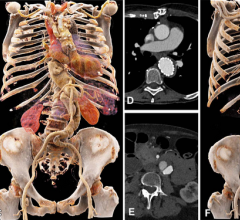

July 13, 2023 — New computed tomography (CT) technology allows for a comprehensive, simultaneous evaluation of lung ...